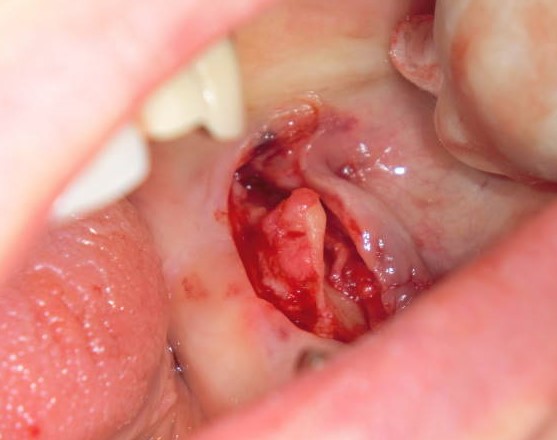

(1)下顎隆起

過剰な下顎隆起は義歯の製作、着脱などに大きな支障となります。

その様な場合、下顎隆起形成術が必要となります。

局所麻酔下に20分ほどで終わり、術後の痛みも余りありません。